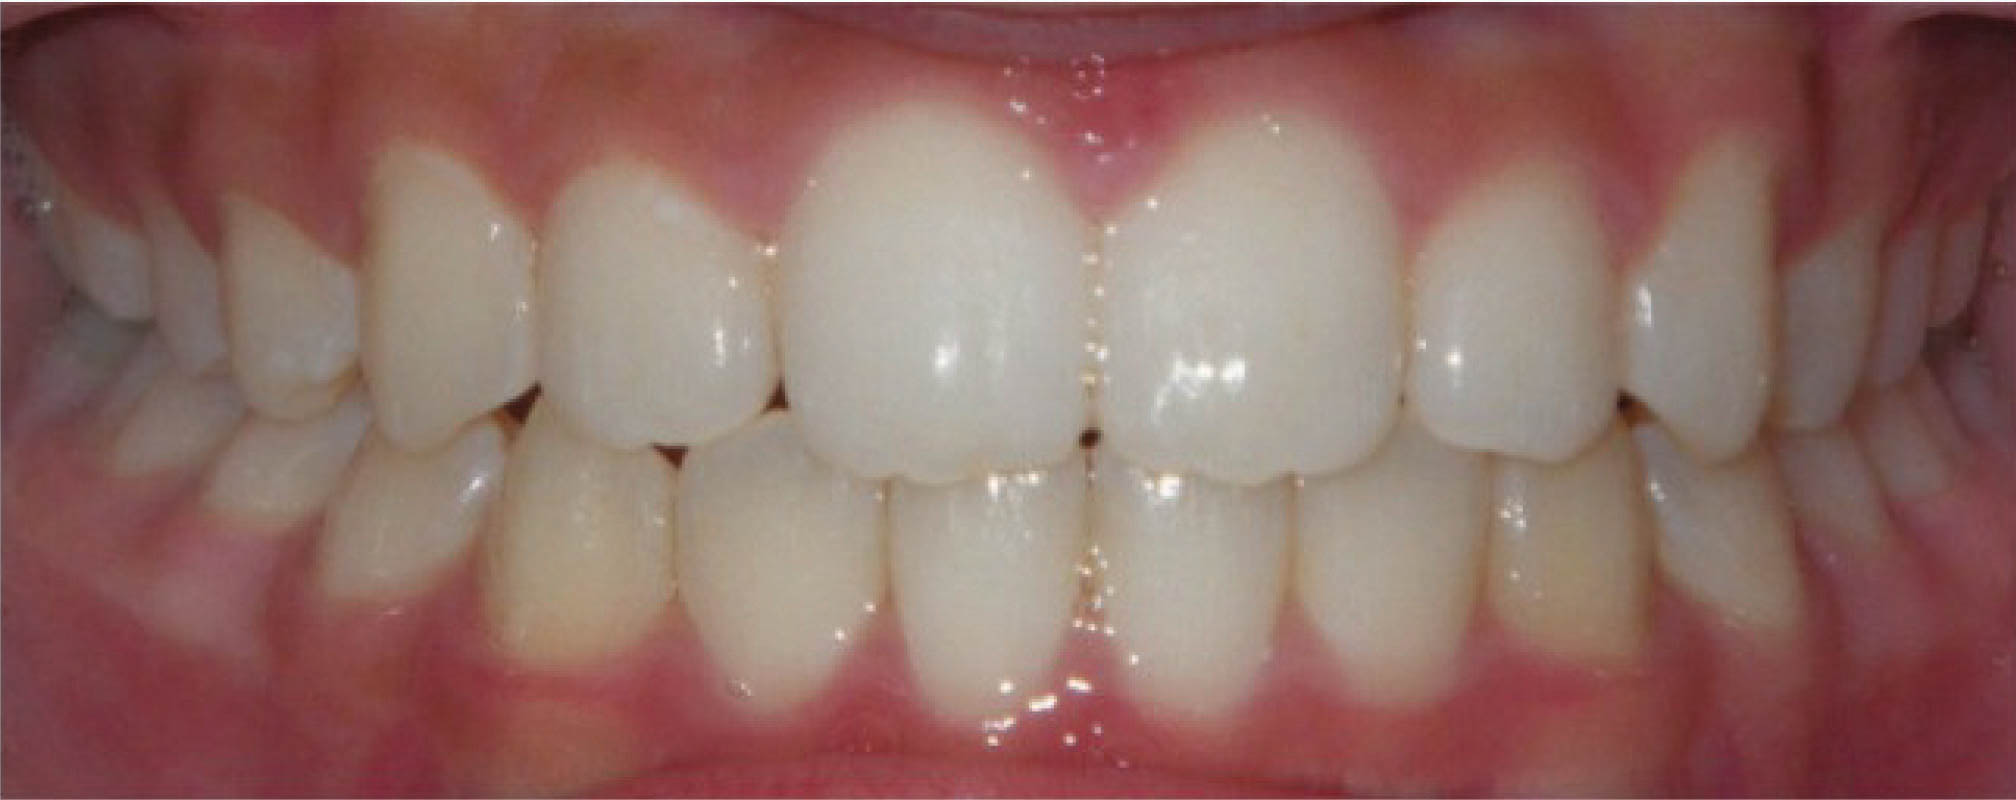

در بیماری که در شکل 38-6 مشاهده میکنید، یعنی بیماری که سانترالهای بالا او از هم به صورت تیپینگ دور شدهاند، درمان با الاینر خیلی عالی میشود، و تصویر آخر نرم افزار به نتیجه درمان خیلی شبیه میشود (شکل 39-6 و 40-6).

شکل 38-6

شکل 39-6

شکل 40-6